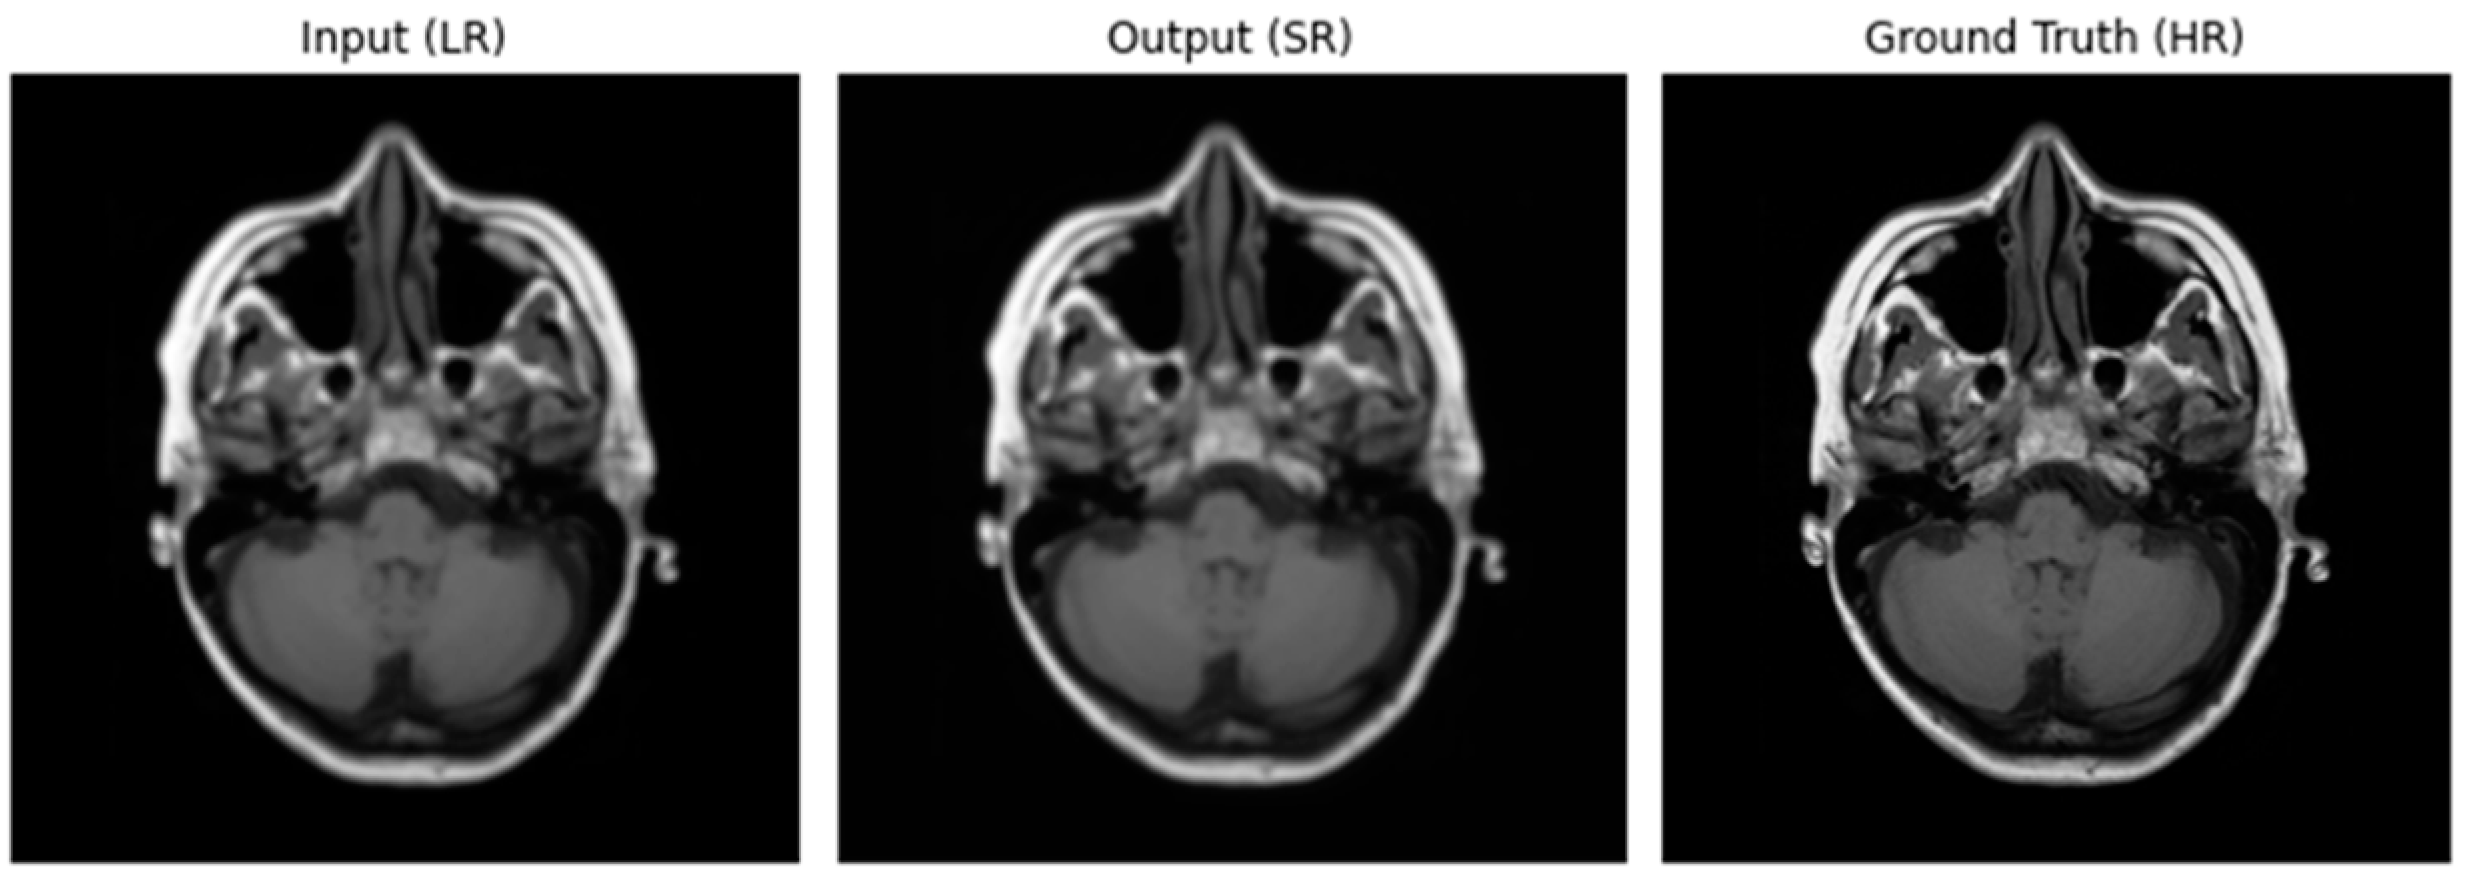

3.2. Performance of ADAM Optimizer and Use of Loss Functions Using Super Resolution Convolution Neural Network (SRCNN)

3.3. Performance of ADAM Optimizer and Use of Loss Functions Using Super Resolution Residual Network (SR ResNet)

3.4. Comparative Analysis Table of SRCNN and SR ResNet with ADAM Optimizer and Loss Functions